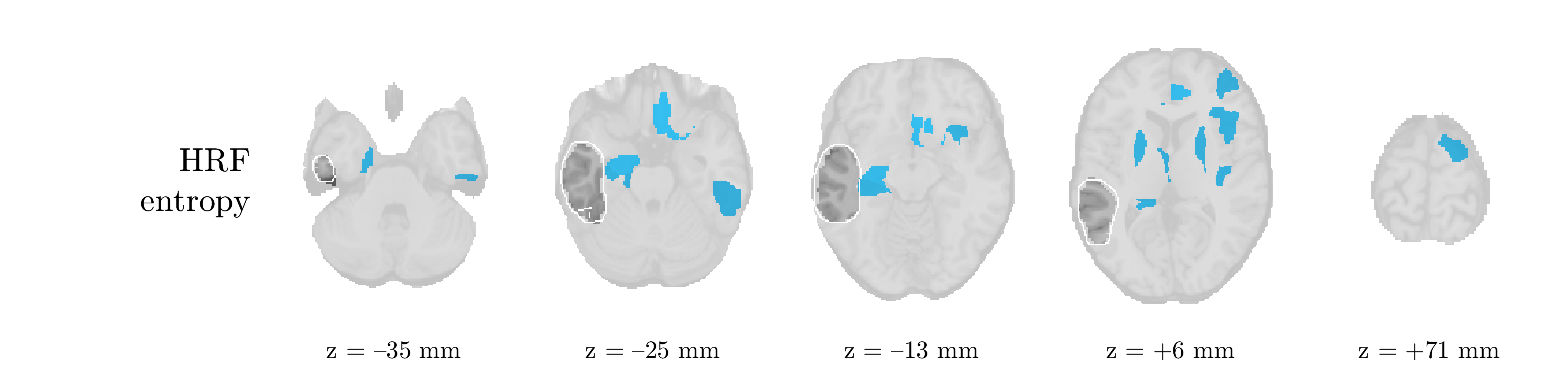

Patient 2

We analyze the solution with sources, and show the results in Figure 3 and 4. As for patient 1, we found a source which is strongly correlated to the MWF envelope, and which had a mostly low-frequency behavior characteristic for spikes. The topography is mostly uninformative, and does not clearly correspond to the patient’s clinical data. The third source is mostly present at both sides of the head, is very sparsely active in time, and has a high-frequency content: this is most likely an artifact due to the neck muscles. Again, there is one of the highest-entropy HRFs which belongs to a ROI in the IOZ. Now, the waveform is clearly resolved from the other HRFs, through the strong initial dip (before 0 seconds). Such a dip is sometimes observed in HRFs, but its underlying physiological mechanism is not yet fully understood. It is possible that this dip reflects altered vascular autoregulation near the IOZ (cfr. the explanation in the Section 1 of the main text), or a rapid depletion in oxygen due to IED generation (before the IED becomes visible on the EEG). Figure 4 furthermore shows that the IED-related component is significantly active in parts of the IOZ, and deactive in others. As mentioned earlier, this deactivation may or may not be due to errors in sign correction. Interestingly, the ROI with the high alteration in neurovascular coupling is distinct from both the activated and deactivated ROIs.